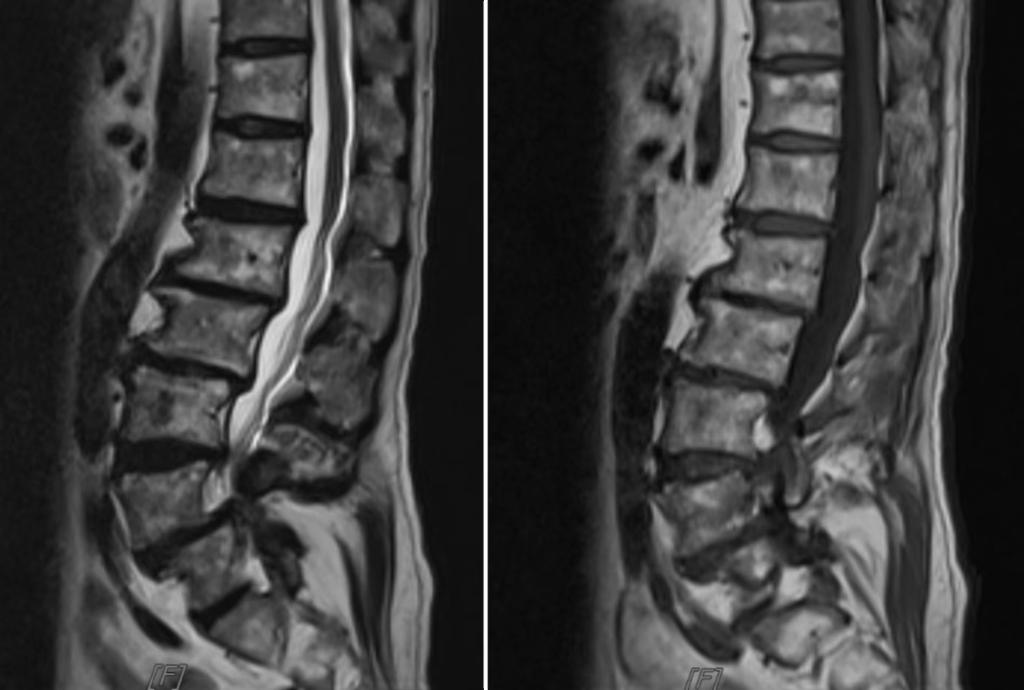

术前腰椎X线片和MRI

73岁的男性患者因“长期腰痛伴双下肢无力10余年”就诊于我医院运动医学科脊柱微创门诊。经过详细检查和评估后发现其存在腰3~骶1(L3-S1)多节段椎间盘突出、腰椎滑脱、椎管狭窄,退变性侧弯等问题,面对如此复杂的病情,柏传毅教授决定采用多窗口经肌间隙入路技术进行微创手术治疗,同时完成椎间盘减压,椎间隙固定融合,腰椎不稳定及侧凸矫形。在小通道多窗口经多个肌间隙,分别对3个节段病变椎间盘减压,椎间隙融合固定,并对脊柱的侧弯和滑脱矫形,充分体现了微创手术效果好、创伤小、康复快的特点。较以往观念,多节段脊柱无法做微创的观念,在熟练掌握传统微创技术下提出了多窗口经肌间隙入路技术,可以完成3节段及以上的椎间盘减压,椎间隙固定融合,脊柱不稳定及侧凸矫形等手术,对于高龄患者,多节段腰椎疾病及现在血源短缺的医疗环境下相对于传统手术有很大的优势。